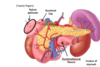

Describe the anatomy of the pacreas

- Locations = right side - lies transversly across poterior abdomen

- Retroperitoneal organ

Parts

- Head - has an uncinate process

- Neck

- Body

- Tail - lies closely to the hilum of the spleen

What are the anatomical relations of the pancreas

Posterioly lies

- Abdominal aorta

- Right and left kidney and adrenal glands

- IVC

- Bile duct

- Superior Mesenteric vessesl

- Part of the portal system

Anteirorly - lies Stomach

Doudenum - surrounds heads

Superior-posterioly - splenic vessels

What are the functions of the pancrea

- Excorine function: Acinar cells - release pancratic digestive enzymes into main pancreatic duct

- Endocrine functions: Islets of langerhands - Releases insulin and glucagon into the blood stream

What is the autonomic supply to the pancreas

Vagus nerve (all glands are supplied by parasympathetics